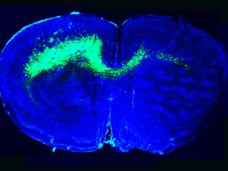

Brain Tumors Hack the Neuronal Microenvironment in Multiple Ways to Drive Tumor Growth

A glioblastoma genetic screen done in mice shows how very different pathways can be altered by different variants of the same key gene—in this case PIK3CA. Tumor cells may even act on neighboring, wild type cells to promote tumorigenesis. The work was led by Drs. Benjamin Deneen, Kenneth Scott, and Gordon Mills, researchers from NCI’s Cancer Target Discovery and Development (CTD^2) Network.